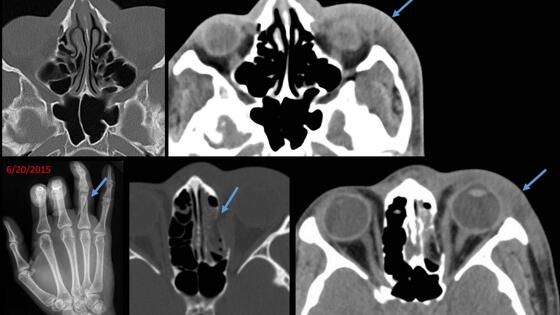

Медики из Женской больницы имени Бригэма определили признаки, по которым рентгенолог может понять, что его пациент – жертва домашнего насилия. Результатами своего исследования ученые поделились на ежегодном съезде Радиологического общества Северной Америки. «Рентгенологи должны осознавать, что жестокость со стороны близкого человека – распространенная проблема. С ней сталкивается каждая четвертая женщина в Соединенных Штатах. Так что у многих наших пациентов может быть такая несчастливая история», – рассказала один из авторов работы, рентгенолог из Женской больницы имени Бригэма Элизабет Джордж. Исследование началось с того, что в Женскую больницу обратилась молодая женщина с переломом носовой кости, наложенным на похожий залеченный перелом. Просмотрев данные о пациентке, врачи обнаружили также недавний перелом запястья. Такие повторяющиеся травмы заставили врачей заподозрить насилие. В ходе работы ученые проанализировали медицинские карточки пациентов, заявлявших о случаях домашнего или сексуального насилия с января по октябрь 2016 года, и обнаружили несколько характерных повреждений. «На рентгеновских снимках мы часто замечали повреждения мягких тканей и переломы конечностей, особенно рук, которые происходят при попытках защититься. Другие часто встречающиеся травмы относятся к повреждению костей лица как легко доступной области. Такие травмы могут предупредить рентгенолога о том, что, возможно, он имеет дело со случаем домашнего насилия», – заключила Джордж.